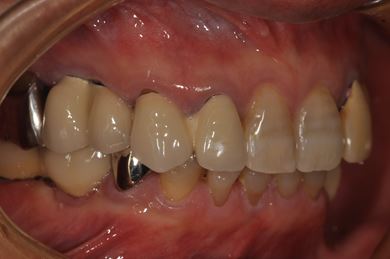

インプラントの症例写真 IMPLANT

骨再生インプラント治療

| 性別/年齢 | 男性 / 58歳 | ||||||||||||||||||||||||||||||||

| 主訴 | ブリッジがだめになったため、現在は部分入れ歯を使用しているが、インプラント治療を検討している。 | ||||||||||||||||||||||||||||||||

| 治療方針 | 左上奥の欠損部分をインプラント治療にて、機能的・審美的回復を行う。 | ||||||||||||||||||||||||||||||||

| 治療内容 | インプラント3本(GBR)、ハイブリッドセラミッククラウン3本 | ||||||||||||||||||||||||||||||||

| 総治療費 | 791,520円 | ||||||||||||||||||||||||||||||||

| 治療期間 | 10ヶ月 |